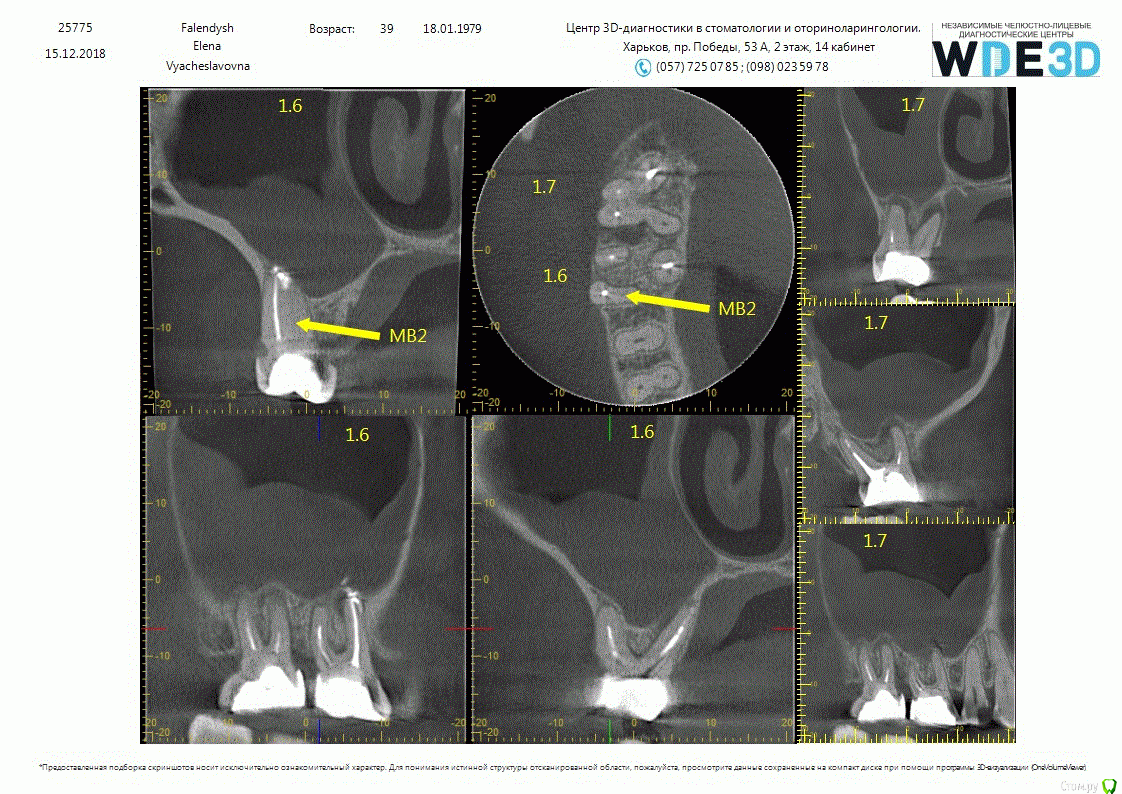

RUVIK Опубликовано 20 декабря, 2018 Поделиться Опубликовано 20 декабря, 2018 всем доброго дня. Интересует мнение профессионалов, была в нескольких клиниках. Болел 6 и 7й зуб которые ранее пломбировались (сейчас перестал, есть время принять решение), Каждый врач ставит свой диагноз, от перелечивания зубов до удаления,чистки гайморовой пазухи и наращивания кости. прикрепляю файла в разных форматах - фото Ссылка на комментарий

St. Опубликовано 20 декабря, 2018 Поделиться Опубликовано 20 декабря, 2018 Вариантов 2, диаметрально противоположных.1й Консервативный. перелечивать каналы ( есть пропущенные) и наблюдать потом 6 и 12 мес как заживает кость и уходит воспаление из гайморовой. 2й Радикальный. Если не хотите перелечивать , удаление с последующим синуслифтингом и имплантацией 2 Ссылка на комментарий

RUVIK Опубликовано 21 декабря, 2018 Автор Поделиться Опубликовано 21 декабря, 2018 Вот прицельные снимки под микроскопом .Что скажите ,стоит ли пробовать перелечивать каналы или шансов нет? Ссылка на комментарий

RUVIK Опубликовано 21 декабря, 2018 Автор Поделиться Опубликовано 21 декабря, 2018 (изменено) Вот прицельные снимки под микроскопом .Что скажите ,стоит ли пробовать перелечивать каналы или шансов нет? Изменено 21 декабря, 2018 пользователем RUVIK Ссылка на комментарий